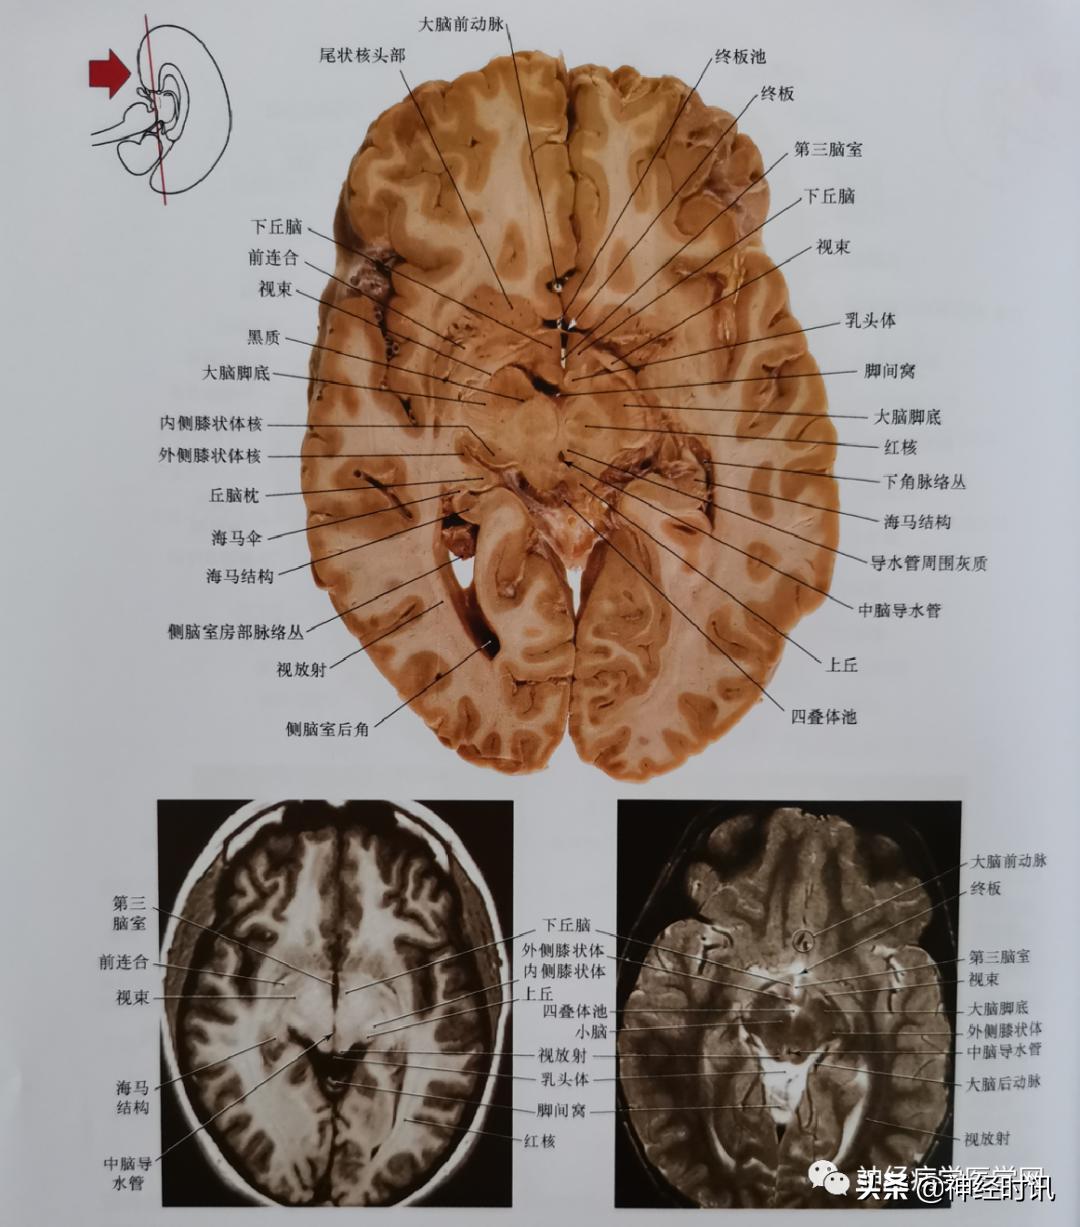

图11 通过前联合、穹窿柱、部分内侧及外侧膝状体核、上丘平面的轴位影像,苍白球的中间及外侧段,在这张切片上都可以看到。注意丘脑上核的位置,其毗邻内囊后肢,压缩形成大脑脚。

图12 通过视束、下丘脑、乳头体、红核、上丘、内侧及外侧膝状体核平面的轴位影像。注意前连合与视束(切片与MRI)看起来很相似,但是从空间上可以分辨出来是两个结构。